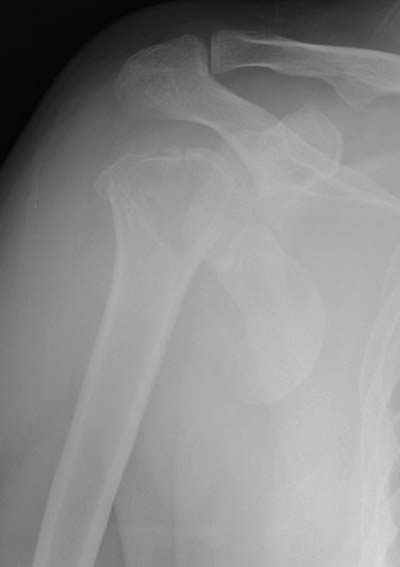

Здесь случай перелома-вывиха плеча, больному 56 лет, после "дважды" закрытой неудачной репозиции, опять же ургентно взяли в операционную, после полного общего обезболивания попытались сделать репозицию, и фиксацию провели спицами.

Больной находился в повязке, примерно напоминяющей косыночную, рекомендованы движения в локтевом суставе и маятниковые движения в плече, спицы удалены в три недели (были случаи миграции)

Больной амбулаторный, предупрежден на случай осложнения АВН головки.

|

Уважаемые коллеги

сделать закрытую репозицию с помощью ЭОПа совсем не сложно, после этого еще проще провести 3-6 спиц и получить красивую рентгенограмму. Есть только небольшая проблема это ROTATOR CUFF. Для плечевого сустава только костное восстановление не достаточно. для функции плечевого сустава нужны вращатели.

Давайте представим себе состояние манжетки вращателей после вывиха плеча, а еще и с отрывным переломом бугров. Головка может и прирастет, еесли не будет аваскулярного некроза, но хорошего функционального результата не ждите.

Висеть будет красиво. У людей физически активного периода жизни нужно открыть, восстановить костную анатомию и восстановить сухожильный аппарат.

В этом плане Locking plate очень хороша так как позволяет начать движения сразу после операции.

Клинические снимки - 3 недели после операции

с уважением М. Беренштейн